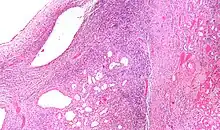

| Micrograph of a cystic nephroma (left of image). Normal kidney is seen on the right. H&E stain. | |

A cystic nephroma, also known as multilocular cystic nephroma, mixed epithelial stromal tumour (MEST) and renal epithelial stromal tumour (REST),[1] is a type of rare benign kidney tumour.

Cystic nephromas are diagnosed by biopsy or excision. It is important to correctly diagnose them as, radiologically, they may mimic the appearance of a renal cell carcinoma that is cystic.[2]